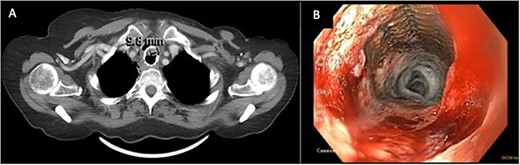

A 71-year-old female presented in May 2020 with a 6-month history of progressive dysphagia and weight loss. Her past medical history was significant for recurrent ductal carcinoma in situ of the left breast. She was a never smoker. Esophagogastroduodenoscopy (EGD) showed a proximal circumferential mass with friable mucosa and ulcerations at 15 cm (Fig. 1A–D). Computed tomography (CT) imaging showed significant soft tissue thickening and luminal narrowing of the esophagus from the sternoclavicular joints to the carina (Fig. 2E). An esophageal stent was placed to support nutrition, which improved the patient’s dysphagia. Biopsy confirmed invasive SCC. Subsequent positron emission tomography imaging revealed 18-fluorodeoxyglucose-avid mediastinal, bilateral supraclavicular, and subdiaphragmatic lymph nodes. Bronchoscopy showed no evidence of tumor invasion into the airway.

(A–D) EDG images showing circumferential esophageal mass with friable mucosa and ulcerations. (E) CT chest showing marked soft tissue thickening with luminal narrowing in the upper esophagus, which extended to a level below the carina.